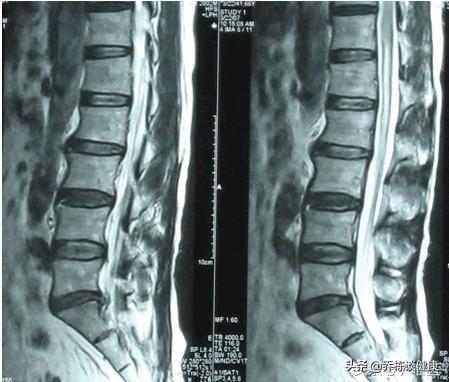

脊柱は全体ではなく、いくつかの椎骨と椎間板があり、主にこの椎間板のことを言いますが、この椎間板は「髄核」と「線維性環状骨」の2つに分かれており、いわゆるヘルニアとは、髄核が線維性環状骨を突き破って流れ出し、神経根や脊髄を刺激・圧迫することで様々な症状を引き起こします。いわゆるヘルニアとは、髄核が環椎を突き破って流れ出し、神経根や脊髄を刺激・圧迫することを指す。

このヘルニアは、加齢、椎間板変性のために発生しますが、不健康な姿勢と重いものを持ち上げると、2年間の休養のため、それ自体の患者は、刺激によって引き起こされる神経根の椎間板ヘルニアを軽減し、水腫と神経根の炎症反応の程度を緩和し、この時点で、重いものを運ぶことを余儀なくされた場合、それは再び条件の安定化が再発した可能性が高い、腰痛や下肢痛の出現は、原因の生活に影響を与える。簡単なことだ:

安静は炎症反応を抑えるだけだが、線維輪の破裂は残っており、適切な圧力をかけなければ、髄質が流れ出て神経根を刺激・圧迫し、症状が再発することもある。

腰椎症には多くの原因があり、腰椎筋肉疲労、腰椎椎間板ヘルニア、急性腰椎捻挫などがあります。通常、長時間の座位や立位を避け、腰椎に体重がかからないようにします。腰椎椎間板ヘルニア(膨隆):一般的に腰痛症として知られ、漢方麻痺のカテゴリに属し、それは椎間板(環状線維症)破裂髄核突出圧迫神経根の腰痛症、整形外科的難病をもたらす。この病気の発生と腎臓の経絡の損失、緊張の傷害、不適切な労働、経絡の閉塞への感情の動揺、気と血の流れが悪くなり、椎間板の湿潤の損失と変性が生じます。もし不適切な労働は、タイムリーな治療や病気や悪の遅延の再発エピソードの不適切な治療でない場合は、累積損傷を形成することは非常に簡単ですが、光は腰椎と脚の痛み、下肢のしびれ、歩行困難、非常に痛いです、重い筋肉萎縮肢寒さ、尿や便失禁、性的機能障害、寝たきりの生活はセルフケアすることはできません。